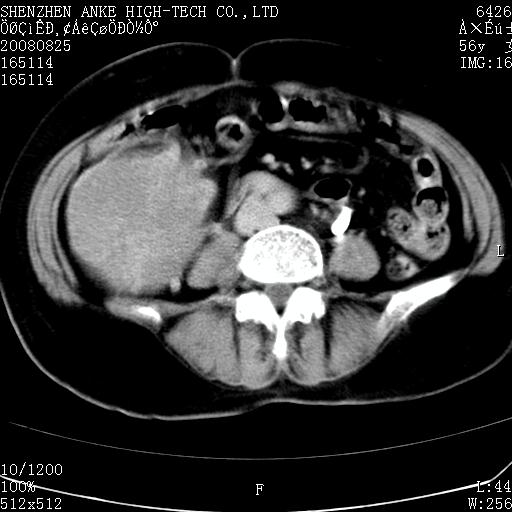

患者,女性,56岁,腰痛3年,查:右腹部约8x10cm肿块,固定,无压痛;8月23日在外院做了平扫,发现右肾巨大肿块(外院具体诊断不祥);今天在我院做了静脉肾盂造影,示:右肾明显增大,分泌功能明显减弱。

支持右巨大肾癌。

1)考虑右肾癌并右肾静脉瘤栓形成。2)脂肪肝。